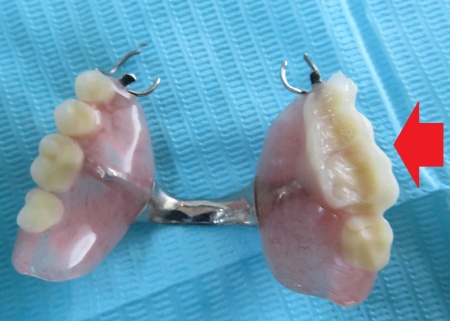

プラスチックの硬化後は、はみ出した余分な部分を丁寧に削り取り、上下の歯が自然に噛み合うように調整を行いながら、表面を丁寧に研磨しました。

最後に修理した入れ歯を装着いただき、見た目や噛み合わせに問題がないか、痛みや違和感がないかなどを確認して、治療を終了しています。

奥歯でしっかり噛めることを確認しました。